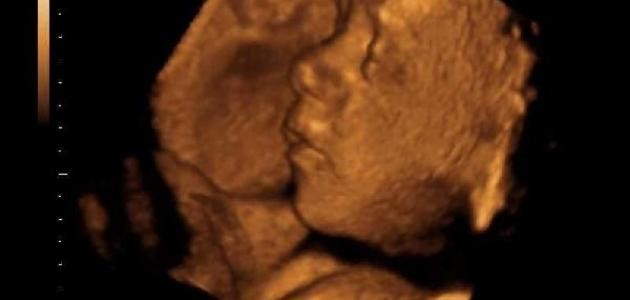

تشوهات الجنين

تشوّهات الجنين أو المعروفة باسم العيوب الخَلقية، هي مشكلة في تكوين الجنين خلال الأشهر الأولى من الحمل، وتتفاوت هذه التشوّهات بين خلل في عمل وظائف الجسم، أو تشوّهات في شكل الجسم وتكوينه، وتؤثر على صحّة الجنين وسلامته، وقد تعرّضه في بعض الأحيان إلى الوفاة، وفي هذا المقال سنعرفكم على علامات تشوّه الجنين.

لتشوهات الجنين أنواع لها أعراض مختلفة فمنها ما يمكن معرفته في الشهور الثلاثة الأولى، والتي تظهر عند تشكُّل أجهزة الجنين، أو أنواع تتم معرفتها بعد ستة شهور من الحمل، ومنها أيضاً ما تظهر بعد الولادة خاصة التي تكون عبارة عن تشوّهات شكلية، كما أنّ منها ما لا يُكتشف إلا بعد فترة من الولادة وهي التشوهات المتعلقة بوظائف الأعضاء، ويستطيع الطبيب معرفة أعراض تشوه الجنين عن طريق الأجهزة المتطورة وهي أجهزة السونار في الأشهر الثلاثة الأولى من الحمل.